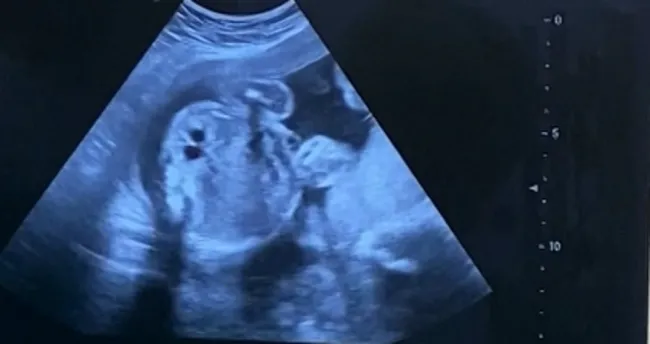

Elazığ’da, Fethi Sekin Şehir Hastanesi tarafından idrar yolunda darlık olan anne karnındaki bebeğe stent takılarak sağlığına kavuşturuldu.Devamı için tıklayınız